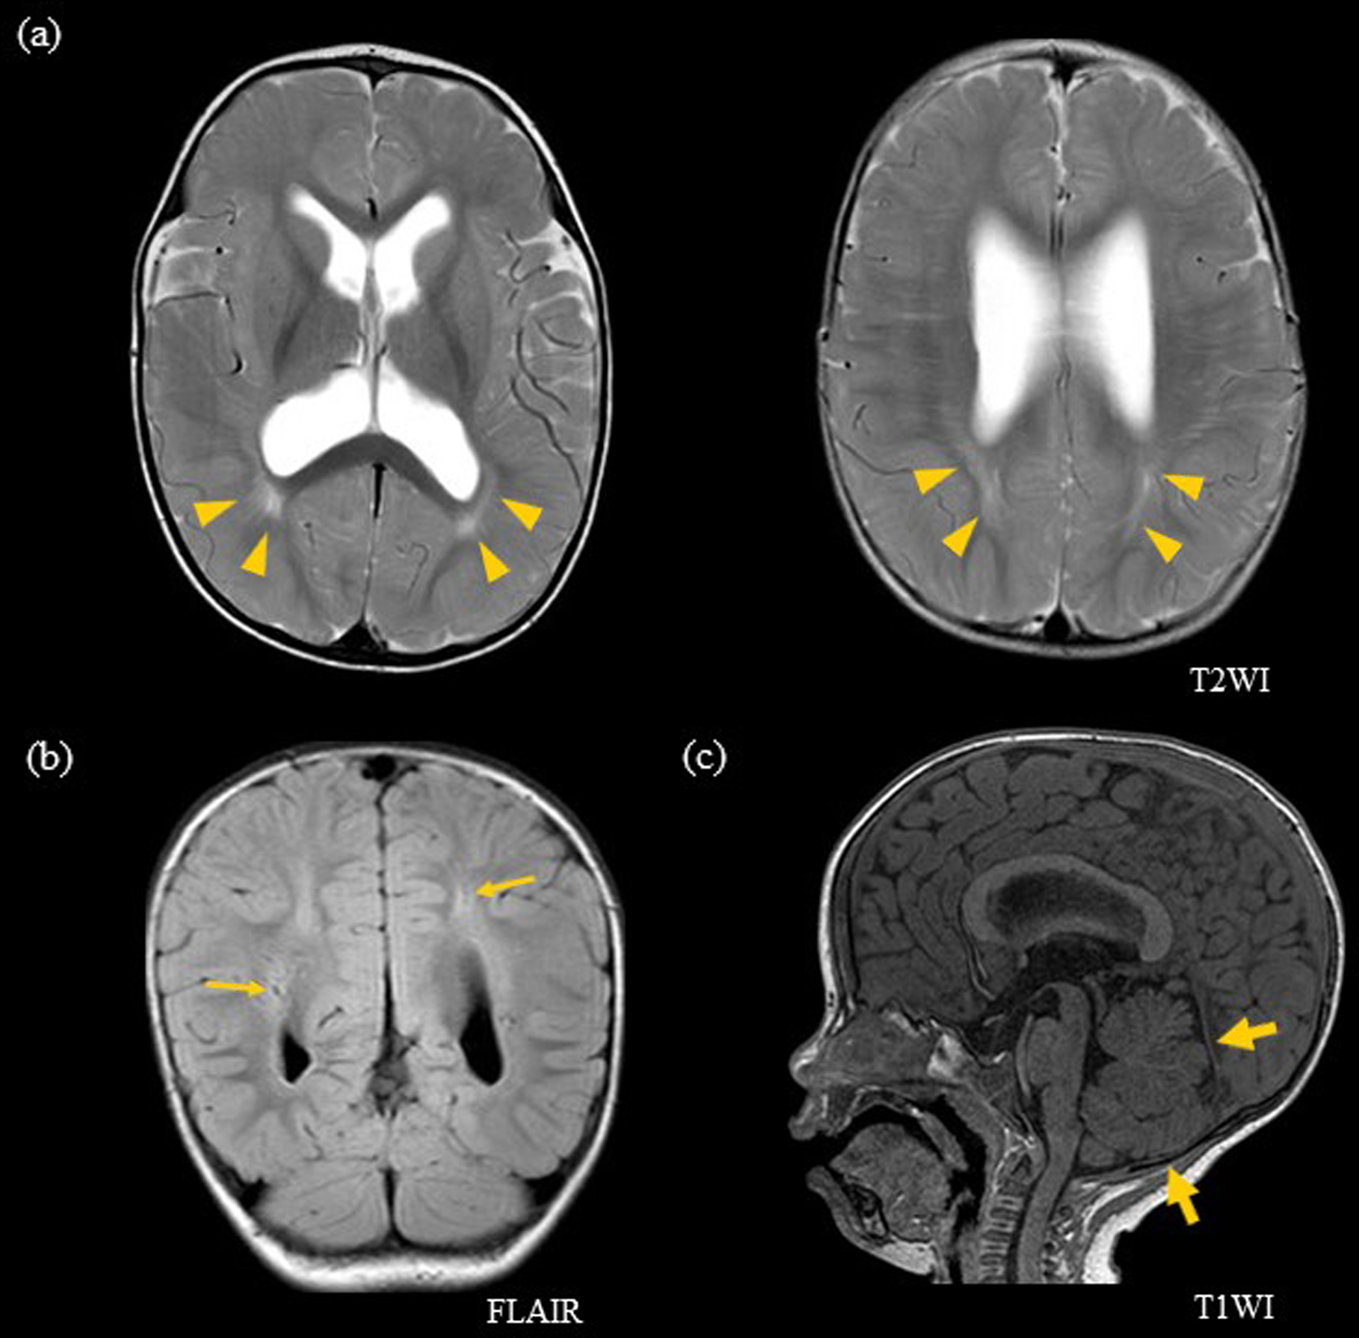

Fig. 1: Head MRI at 10 months of age.

a Axial T2-weighted image and b coronal FLAIR image show hyperintensity in the bilateral periventricular white matter regions (yellow arrowhead) and enlarged periventricular spaces (thin yellow arrow). c Sagittal T1-weighted image shows a narrow posterior fossa (broad yellow arrow)